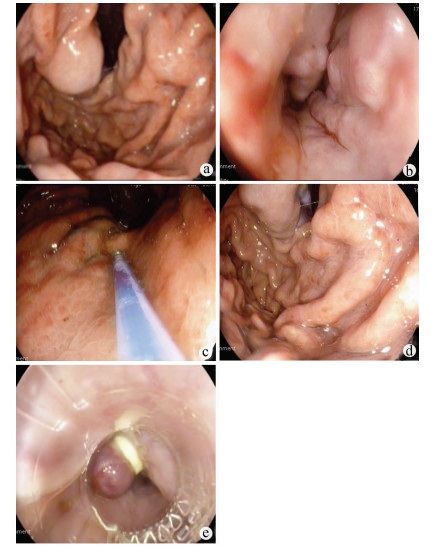

Endoscopic treatment of gastroesophageal varices complicated by posterior reversible encephalopathy syndrome: A case report

Tingting YU, Shanshan JIANG, Mengran ZHU, Yun BAI

2022, 38(1): 177-179. DOI: 10.3969/j.issn.1001-5256.2022.01.030

Abstract(807) HTML (197) PDF (3069KB)(54)

Abstract: